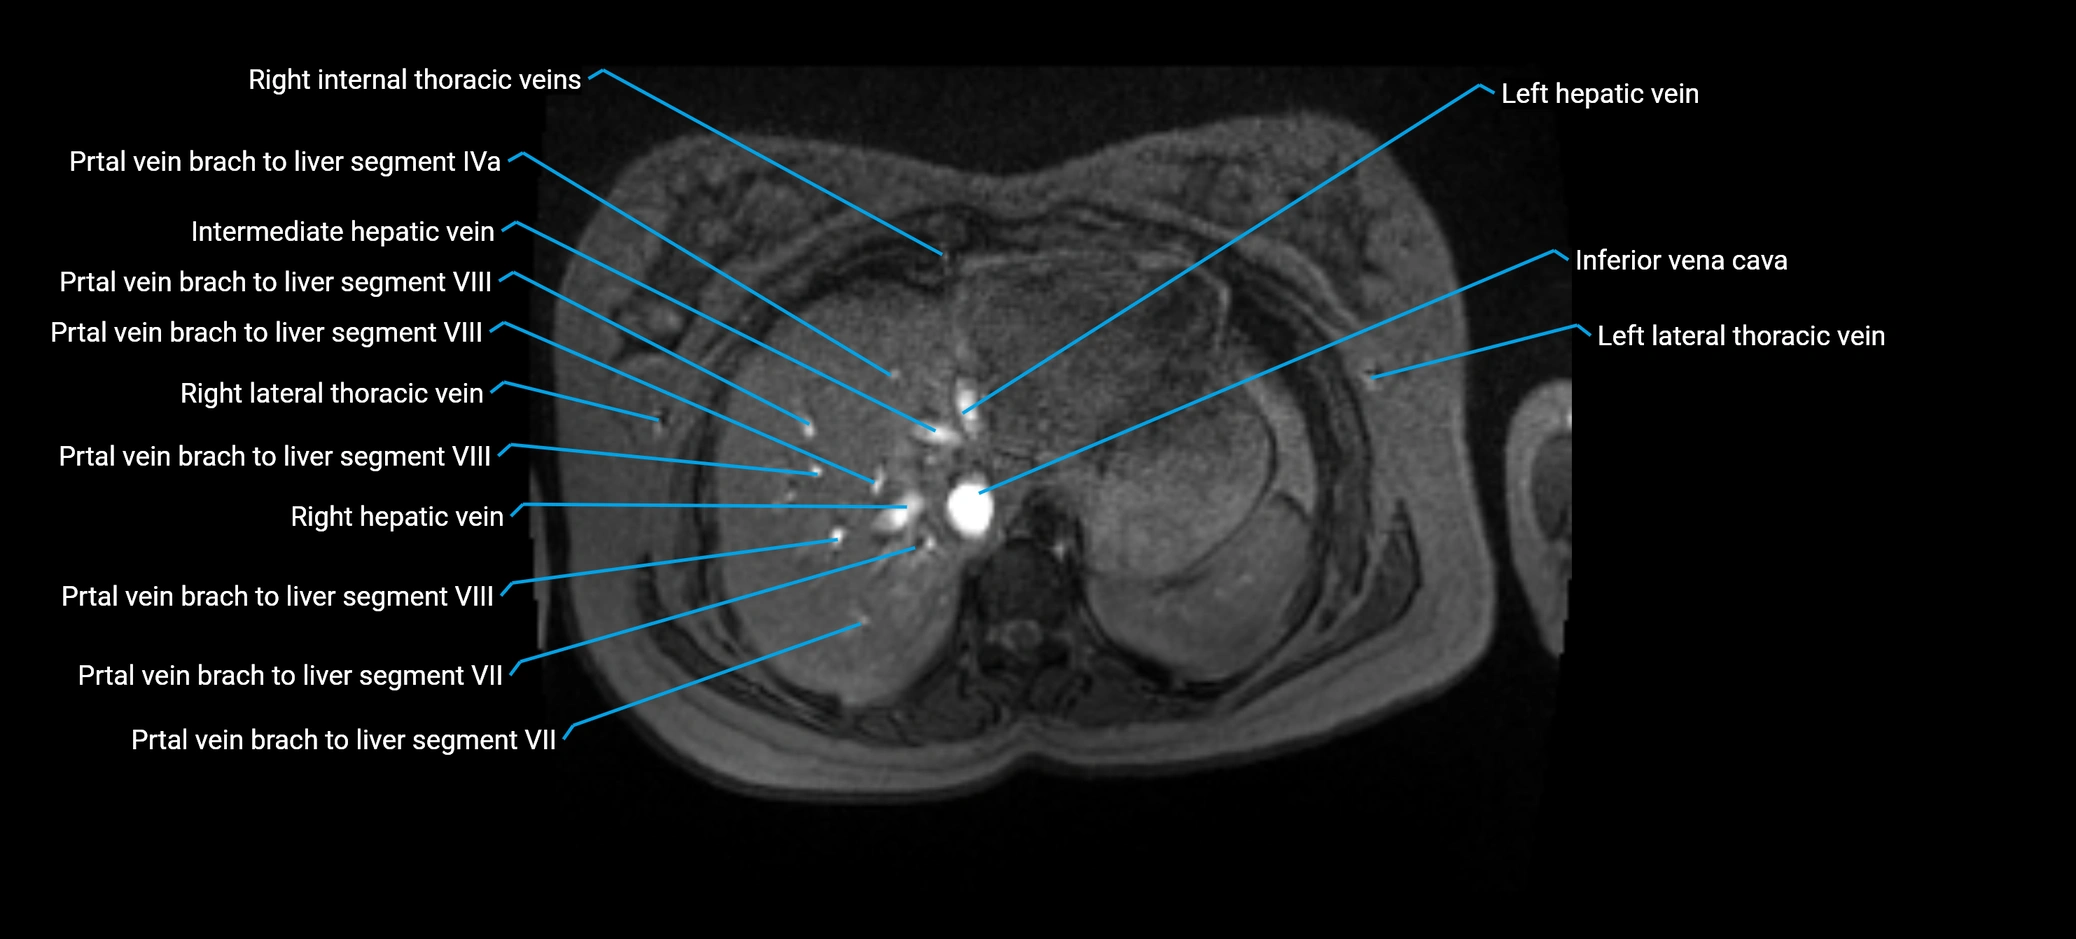

MRV TOF (Time-of-Flight MR Venography):

• Appears as a bright, high-signal vascular channel representing flowing blood

• Clearly shows branching pattern of right portal vein into anterior and posterior branches

• Best in coronal or axial reconstructions for segmental mapping

• No need for contrast, relies on flow-related enhancement

Post-Contrast T1 Fat-Sat GRE:

• Enhances brightly and homogeneously during the portal venous phase

• Clearly delineates branching into segments V and VIII

• Best sequence for evaluating patency, caliber, and anatomic variants

• Early arterial phase: minimal enhancement

• Delayed phase: gradual washout but still brighter than hepatic parenchyma

MRI image

image